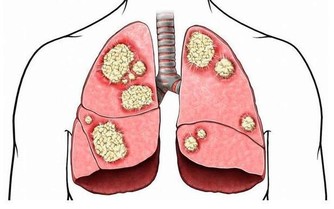

7. 長期飢餓可能導致嚴重甚至致命的並發症

對絕食並且死亡的人進行檢查後,揭示了以下可能的死亡原因:

多器官衰竭;

心室顫動或快速心律,導致心臟泵血作用不佳,並可能導致意識喪失甚至死亡;

嚴重膿毒症(血液中毒),身體因感染而傷害自己的器官和組織。